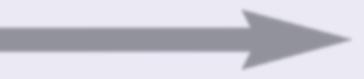

Poiché, in condizioni fisiologiche normali, i globuli bianchi, le cellule dell’ovaio e molte altre cellule del corpo usano per svolgere le loro funzioni il meccanismo di produzione di enzimi che digeriscono il collagene (A), il tumore riesce a diffondersi in modo incontrollato senza che il sistema immunitario possa impedirlo (B). Di fatto si tratta di un inganno: le cellule del cancro sfruttano lo stesso meccanismo usato dalle cellule sane, ma in modo incontrollato.

Salut e (condi zioni f isio logiche n ormal i)

Globulo bianco (Leucocita)

Digestione del tessuto connettivo in condizioni controllate di tempo e spazio

Digestione incontrollata del tessuto connettivo